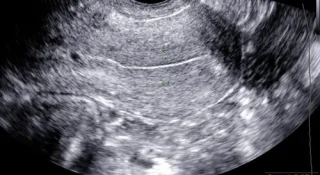

Диагноз ставится на основании беседы с врачом, осмотра на гинекологическом кресле в зеркалах у женщин, анализа мочи, мазка на микрофлору из влагалища или уретры с определением чувствительности к антибиотикам, ультразвукового исследования, цистоскопии и пр.